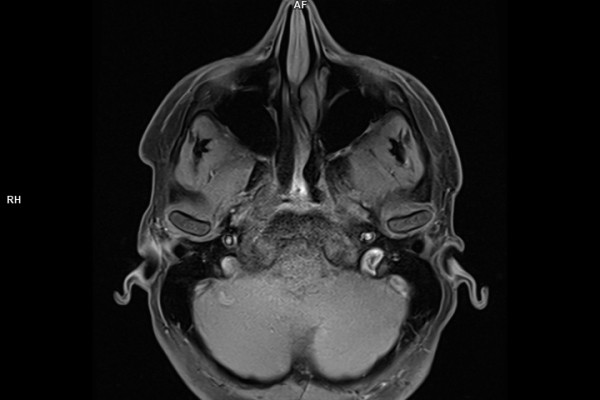

• Neuroradiologie

Die MRT (Magnetresonanztomographie) arbeitet mit Magnetfeldern und Radiowellen und eignet sich besonders für Untersuchungen der Weichteile wie Gehirn, Muskeln oder Gelenke. Die CT (Computertomographie) nutzt Röntgenstrahlen und liefert schnelle, hochauflösende Bilder, insbesondere für Knochen, Lunge oder innere Organe. Die Wahl der jeweiligen Untersuchung richtet sich an das individuelle Krankheitsbild und wird bei der Überweisung festgelegt.